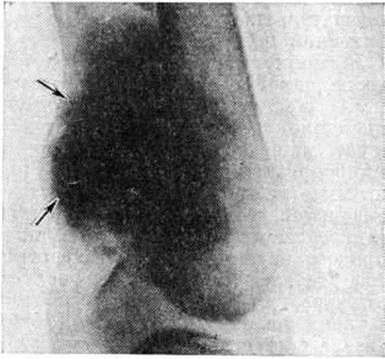

Рис. 2.

Рентгенограмма дистальной части бедренной кости и коленного сустава (боковая проекция) при паростальной саркоме: стрелками указана плотная тень прилежащего к кости опухолевого образования; периостальная реакция не определяется.

В клинические, картине многие исследователи выделяют первоначальную фазу, в течение которой опухоль медленно растёт без выраженных проявлений. Боль, как правило, отсутствует или бывает умеренной. Когда опухоль достигает значительных размеров, появляются симптомы, связанные со сдавлением нервных стволов и кровеносных сосудов, появляются боли, которые усиливаются и становятся постоянными. Рентгенологические картина в начальных стадиях развития опухоли характеризуется наличием в мягких тканях вблизи кости солитарного, грибовидной формы, чётко отграниченного плотного опухолевого образования (рисунок 2). У его полюсов между опухолью и корковым веществом подлежащей кости видна линия просветления. В дальнейшем кость окутывают наподобие муфты опухолевые массы с отчётливыми очертаниями, состоящие как бы из сливающихся шаров и полушарий различных размеров. Структура опухоли в центральной её части плотнее, однороднее, чем в периферической. Периостальной реакции не наблюдается. Паростальная саркома метастазирует гематогенно в лёгкие, где метастазы могут быть обнаружены при рентгенологическое исследовании.